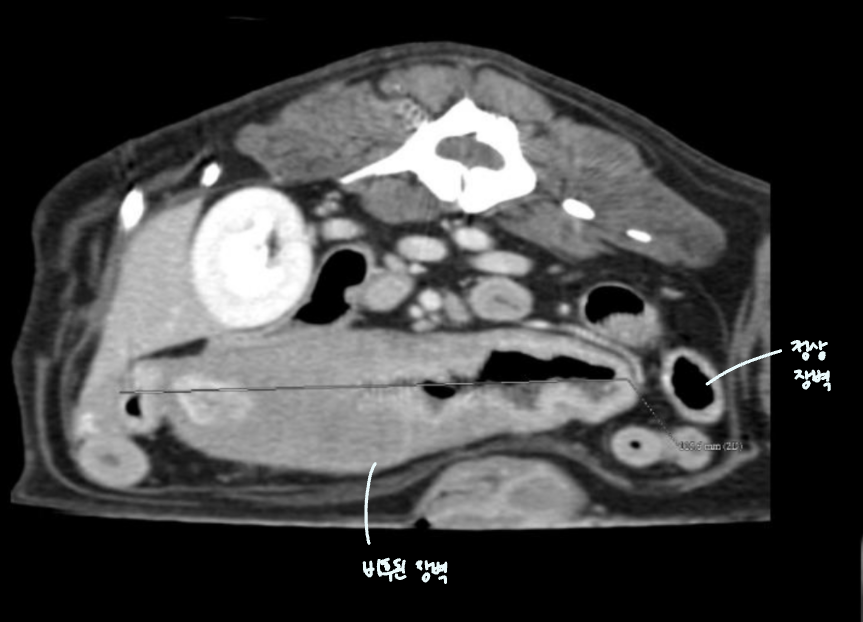

โ ๊ณจ๋ฐ๊ฐ ๋ด์์ ์๋ mass

- 4๊ฐ์์งธ ์ฌํ ๋ณ๋น + ์์๋ถ์ง, ์ฒด์ค ๊ฐ์, ๊ฐํ์ ๊ตฌํ ๋ก ๋ด์.

- Mass๊ฐ ๊ณจ๋ฐ๊ฐ ์์์ ์๋ผ๋ฉด ๊ฒฐ์ฅ๊ณผ ์๋๋ฅผ ๋ฐ์ด๋ด๊ณ , ์ ์ฑ ๋ณ๋น๋ฅผ ์ ๋ฐํจ.

- Leiomyoma๋ก ์ง๋จ๋จ.

โ ๋ด๊ฐ ์์ชฝ์์ ์๋ mass

- ๊ณจ๋ฐ๊ฐ๊ณผ ๋ฌ๋ฆฌ ๋ณต๊ฐ์๋ ์ฌ์ ๊ณต๊ฐ์ด ์์ด, ๋ด๊ฐ ๋ฐ๊นฅ์์ ์๊ธด mass๋ผ๋ฉด ๊ธธ์ ๋ง์ง ์์.

- ๊ทธ๋ฌ๋ ๋ด๊ฐ ์์ ์๊ธด mass๋ผ๋ฉด ๋ถ๋ณ์ด ๊ณ์ ์ถ์ ๋จ.

- ์กฐ์์ ๋ ์ผ์ ํ ๋๋น๋ก ํต๊ณผํ์ง ๋ชปํ๊ณ ๋งํ.